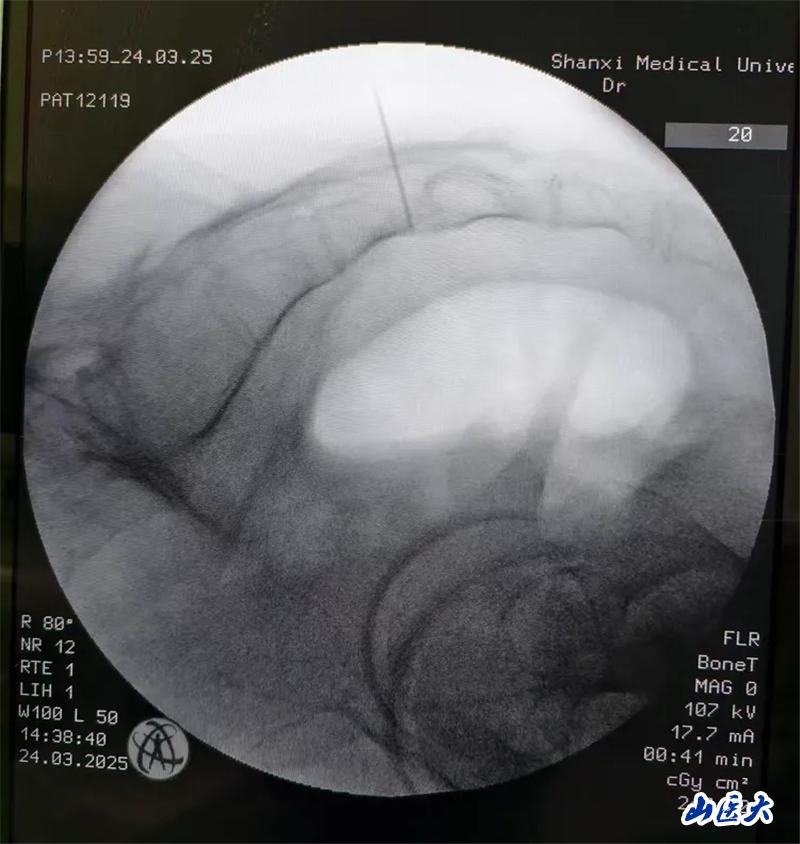

患者是一名中年男性,有着4年以上的尿频、尿急和排尿困难症状,长期和尿不湿、尿管为伴,苦不堪言!做尿动力检查,诊断为:神经源性膀胱和膀胱过度活动症。王璟琦主任医师充分评估病情后,为其进行了骶神经调控术治疗,术后下尿路症状明显改善。手术过程中,患者取俯卧位,显露肛门,便于术中观察电刺激效果。首先,经尾骨尖测量定位确定s3的位置:沿骶骨中线,自尾骨尖向上测量9cm,旁开2cm,为S3骶孔对应体表处。之后在C型臂的引导下准确穿刺S3孔,通过导丝将刺激器导线穿入S3孔内,并根据术中对骶神经刺激后的效果,将导线放入最佳深度。最后,将导线从皮下穿出连接电刺激器。电刺激信号测试满意,三周体外实验,患者排尿改善将二期植入。